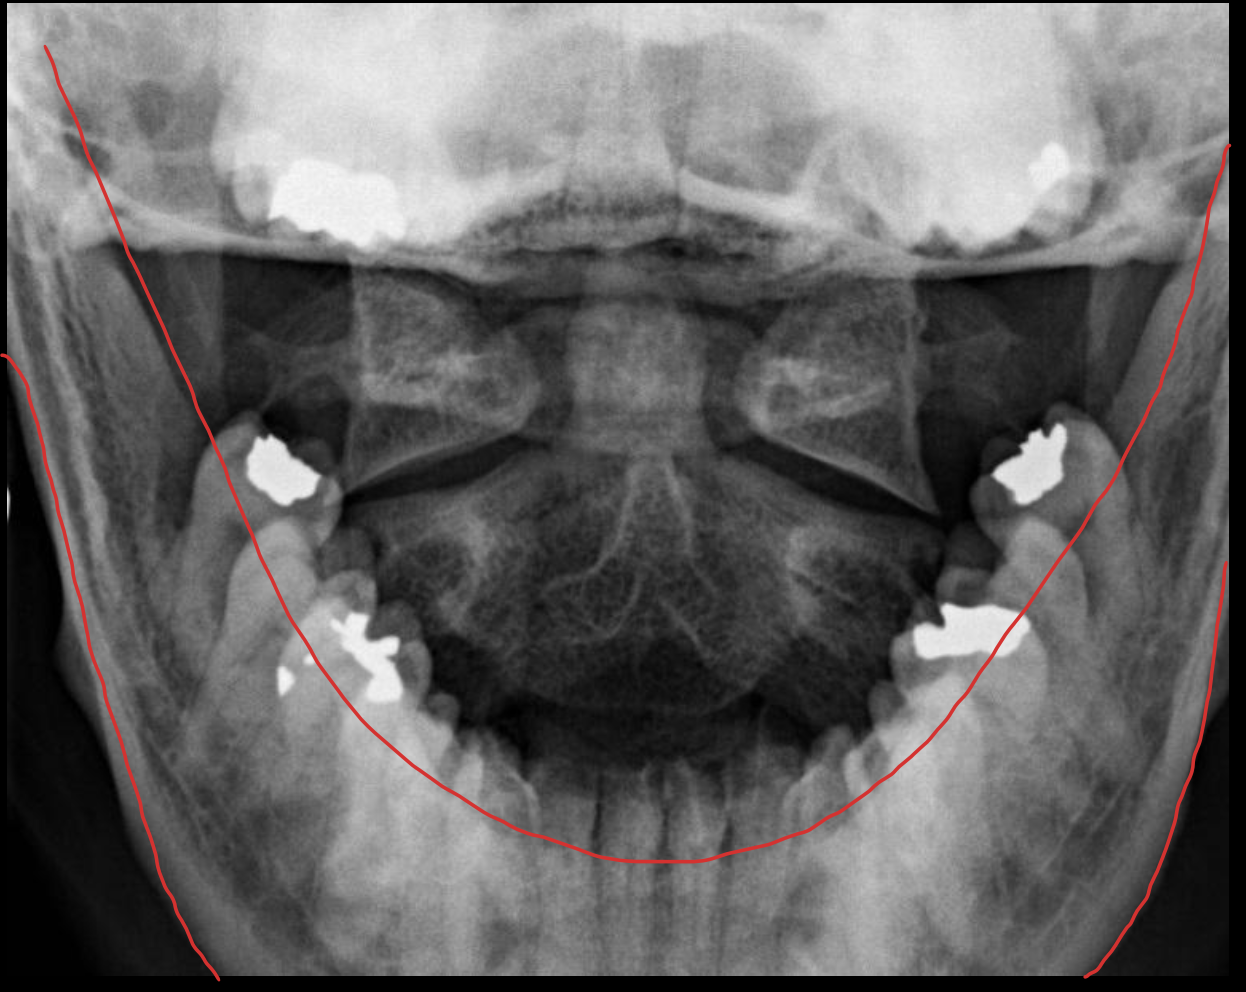

下颌骨

Mandible